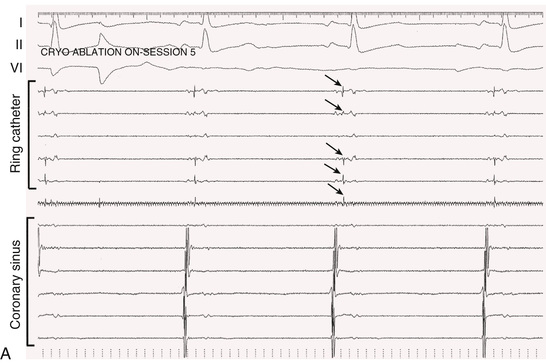

A multielectrode catheter inserted through a central lumen of the cryoballoon catheter often allows recording of PV potentials during an application of cryoenergy. Disappearance or dissociation of PV potentials within the first minute of a cryoenergy application is a strong independent predictor of durable PV isolation64 (Fig. 38.10). Other independent predictors are achieving a balloon temperature of −40°C in less than 60 seconds during an application of cryoenergy and an interval thaw time to 0°C of longer than 10 seconds on completion of a cryoenergy application.64,65